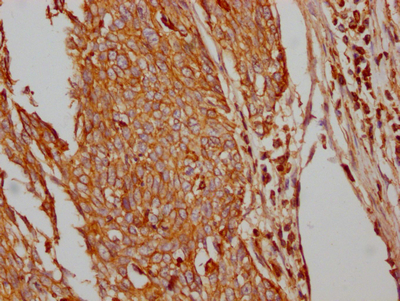

IHC image of CSB-RA297401A0HU diluted at 1:100 and staining in paraffin-embedded human cervical cancer performed on a Leica BondTM system. After dewaxing and hydration, antigen retrieval was mediated by high pressure in a citrate buffer (pH 6.0). Section was blocked with 10% normal goat serum 30min at RT. Then primary antibody (1% BSA) was incubated at 4℃ overnight. The primary is detected by a Goat anti-rabbit IgG polymer labeled by HRP and visualized using 0.05% DAB.